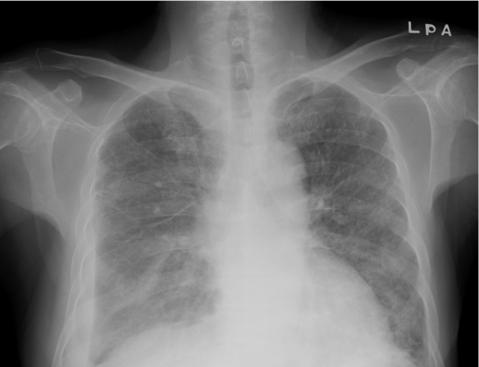

A 60-year-old man presented with cough, sputum, and dyspnea. He had a history of acute myeloid leukemia and hematopoietic stem cell transplantation with chronic renal failure. Chest CT scans showed miliary nodules and patchy consolidations. Histological examination revealed numerous fibrin balls within the alveoli and thickening of the alveolar septum, both of which are typical pathological features of acute fibrinous and organizing pneumonia (AFOP). We report the first case of AFOP following allogeneic hematopoietic stem cell transplantation.